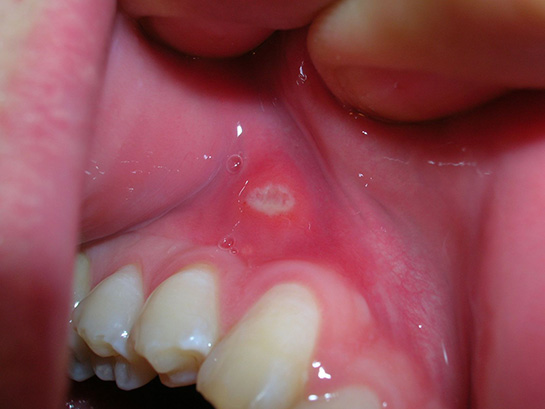

Ağız Yarası Belirtileri ve Tedavisi

Ağız yaraları, ağız içinde veya çevresinde oluşan rahatsız edici yaralardır. Belirtileri arasında ağrı, şişlik ve zorlukla yemek yeme yer alır. Nedenleri arasında yaralanmalar, enfeksiyonlar ve beslenme eksiklikleri bulunur. Tedavi yöntemleri ise yaranın türüne göre değişir.

Ağız yaraları, ağız içinde veya çevresinde meydana gelen çeşitli nedenlerden kaynaklanan yanık, yaralanma veya enfeksiyon gibi durumları ifade eder. Bu yaralar, genellikle rahatsız edici ve acı verici olabilir, bu da günlük yaşamı etkileyebilir. Ağız yaralarının belirtileri, tedavi yöntemleri ve önleyici tedbirler hakkında kapsamlı bir inceleme sunulacaktır. Ağız Yaralarının BelirtileriAğız yaraları, çeşitli belirtilerle kendini gösterebilir. Bu belirtiler, yaranın türüne ve nedenine bağlı olarak değişiklik gösterebilir. Genel olarak görülen belirtiler şunlardır: